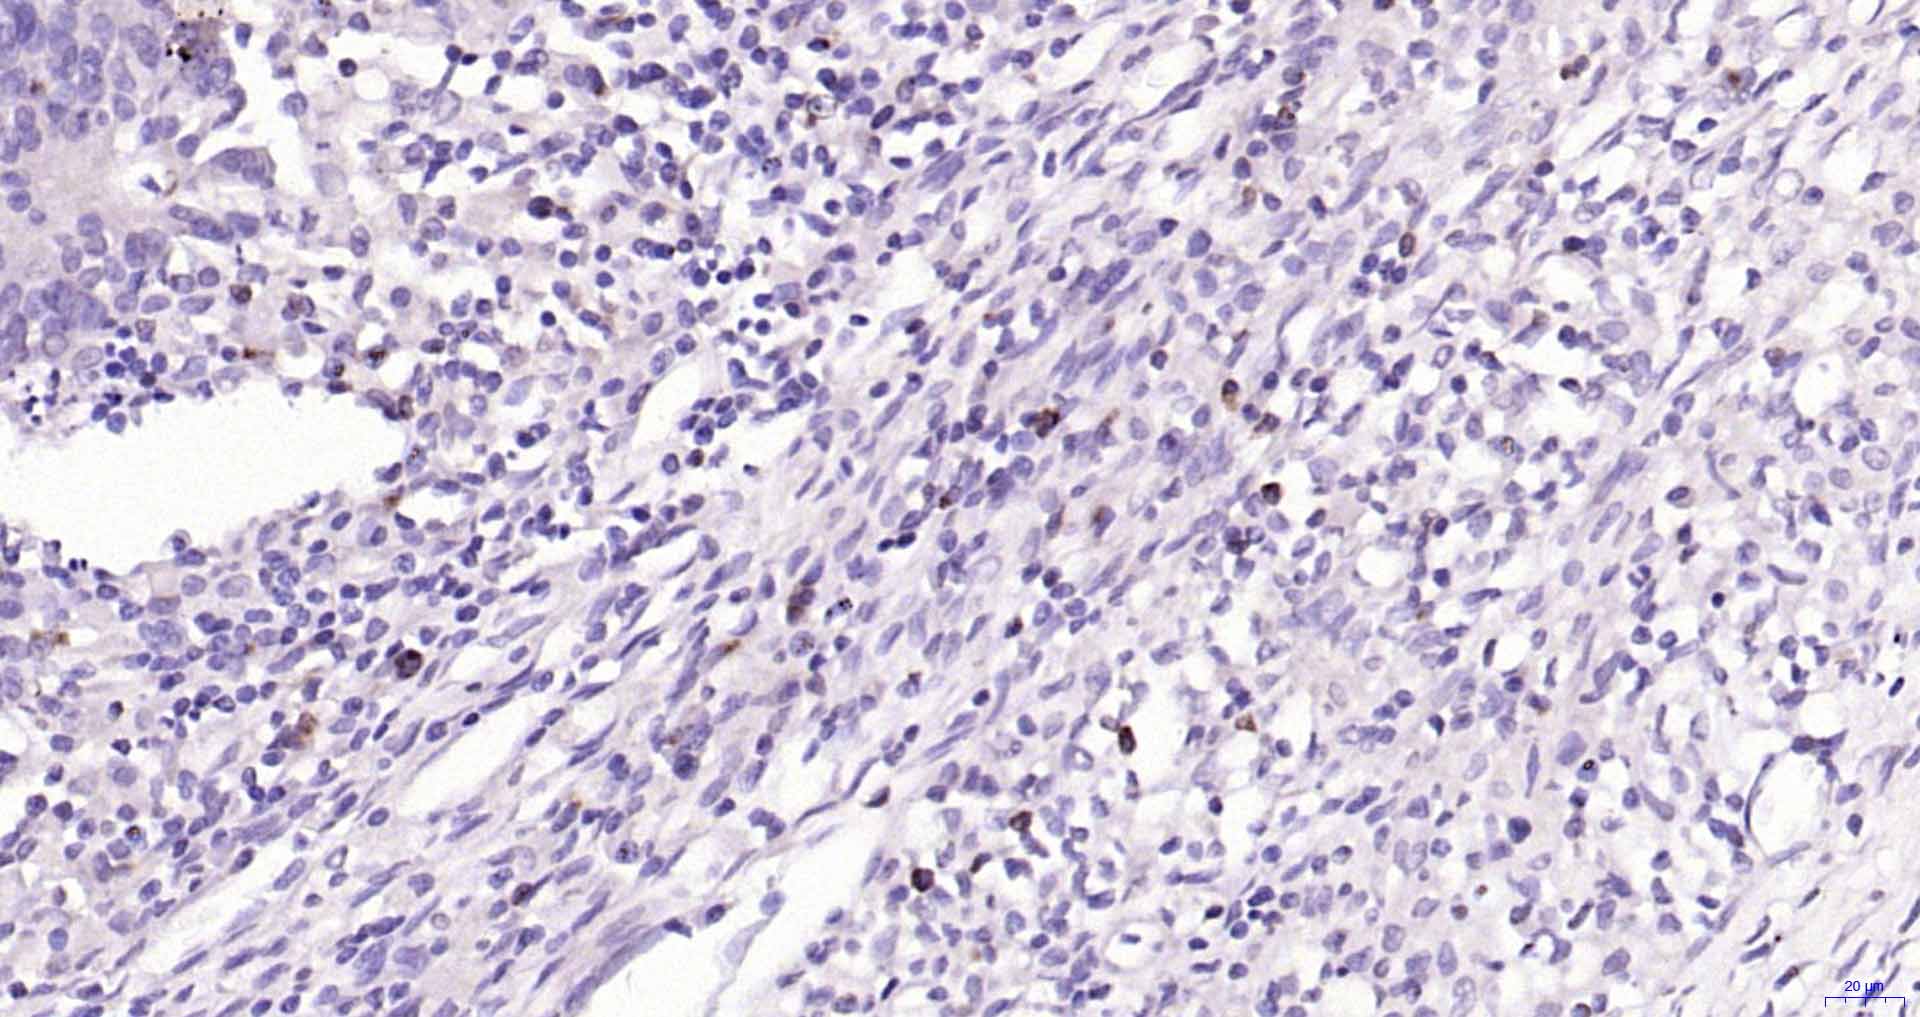

| IHC-P | Human | 1:50-200 | |